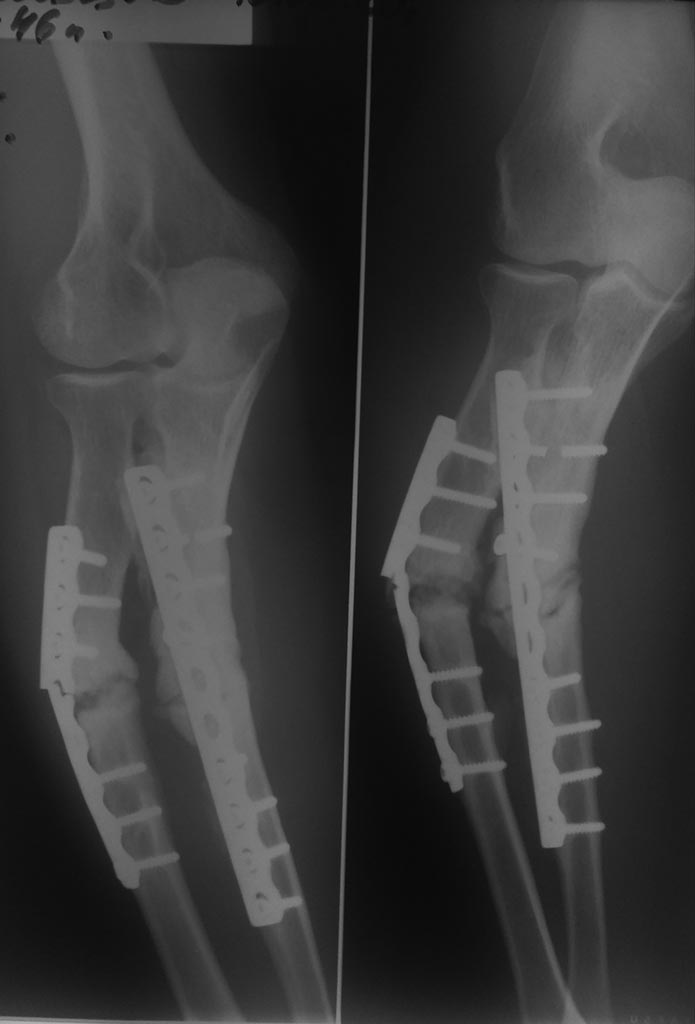

Уважаемые коллеги, нужен совет, что делать в следующей ситуации. Пациент оперирован 5 лет назад по поводу закрытого перелома костей левого предплечья (травма в результате падения на руку дерева при валке леса). Выполнен остеосинтез пластинами. Иммобилизация, реабилитация, фтл. После остеосинтеза переломы не срослись. От повторной операции пациент отказался, щадил руку, носил тутор. Пациенту 45 лет, активный, живет в селе, абсолютно социальный, без в/п. Несколько дней назад почувствовал щелчок и умеренную боль в предплечье. По снимку- ложные суставы обеих костей предплечья, разрушение пластины. Нужен совет по тактике дальнейшего лечения.

Без снимков можно лишь абстрактно посоветовать сделать реостеосинтез либо пластинами, либо гвоздями с блокированием, либо аппаратом.

Снимок

Думаю, нет необходимости обсуждать экзотику и сложные варианты. Удалить пластины. Реостеосинтез. Пластинами. Локтевую кость можно зафиксировать неблокируемым стержнем прямоугольного сечения (типа Богданова).

У пациента нет формирования атрофических ложных суставов, типичная ситуация - перелом хочет срастись, с кровообращением все нормально, да вот стабильности между отломками нет. Пластины держали сколь смогли.

Линии переломов нужно хорошо очистить от м/тканей (можете дополнить костной (ауто) пластикой, хотя, в данном случае, по моему мнению это избыточно) или вообще экономно резецировать линии несращения, верхняя конечность позволяет Вам пойти на укорочение сегмента.

Судя по снимкам, костная пластика не требуется. Переломы "хотели срастись". Интересно узнать почему переломы не срослись. Вы анализировали? Есть первоначальные снимки? Возможно, механизм травмы (падение дерева) имел значение: мягкие ткани скомпрометированы. Иначе рискуете наступить на старые грабли.

Здесь возможны все варианты. Если доступны стержни с блокированием или прямоугольного сечения, а также есть ручная развертка для формирования канала в области несращения, то можно было бы минимально инвазивно удалить пластины, не трогая зону стыка. Дальше все можно сделать закрыто. Дистрактором восстановить ось и длину. И заштифтовать.

Вариант с пластинами открыто не очень привлекатен тем, что из хорошо кровоснабжаемых фрагментов, с хорошими параоссальными источниками кровоснабжения, в результате открытой мобилизации получится стык аваскулярных палок.

Так что вторым по привлекательности вариантом IMHO был бы закрытый чрескостный остеосинтез с восстановлением оси и длины. Его можно сделать даже без удаления пластин.